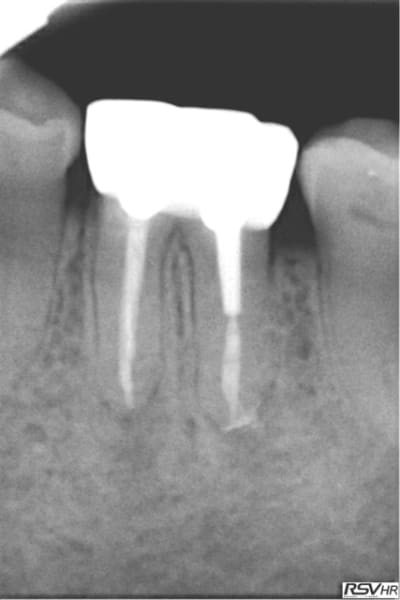

Voici un exemple de couplage microscope opératoire/cbct

RTE 36 en octobre2012 ;3 heures de RTE pour recherche de canaux sous micro inserts ultrasons/il y avait une LIPOE

digue+hypo+système R-endo microméga instruments à mains

vérification au CBCT en 2016

disparition des LIPOE

ici on obtient une guérison apicale